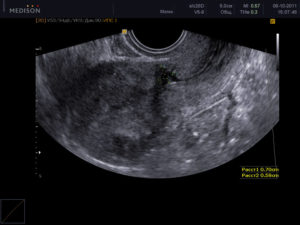

Визуализация рубца после кесарева сечения при проведении трансвагинального УЗИ

Большое внимание уделяется внешнему виду рубца. Его толщина не должна быть меньше 5 мм. На изображении он хорошо различим и выглядит как тонкая темная полоска. Вариацией нормы считается и шрам толщиной 3,5 см.

В идеале рубец должен состоять из мышечной ткани, которая более темная на снимке. У некоторых женщин присутствует соединительная ткань. На изображении возле шва имеется небольшое количество светлых участков.

Несостоятельным считается шов, толщина которого меньше 1,5 мм. Возле рубца имеются неровности и несросшаяся ткань. Сам рубец состоит преимущественно из соединительной ткани.

На снимке такие швы выглядят неровными и размытыми. Четкая темная полоска отсутствует (возможно прослеживание белой полосы). В области рубца наблюдается большое темное пятно.